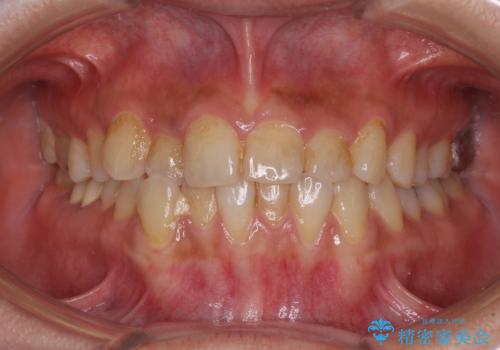

[ インビザライン矯正 ] マウスピースで治す前歯のがたつき

担当医 大元洋佑

![[ インビザライン矯正 ] マウスピースで治す前歯のがたつきの症例 治療前](https://seimitsushinbi.jp/wp/wp-content/uploads/2023/11/C7-500x350.jpg?v=1699665009)

![[ インビザライン矯正 ] マウスピースで治す前歯のがたつきの症例 治療後](https://seimitsushinbi.jp/wp/wp-content/uploads/2023/11/IMG_2993-500x350.jpg?v=1699664953)